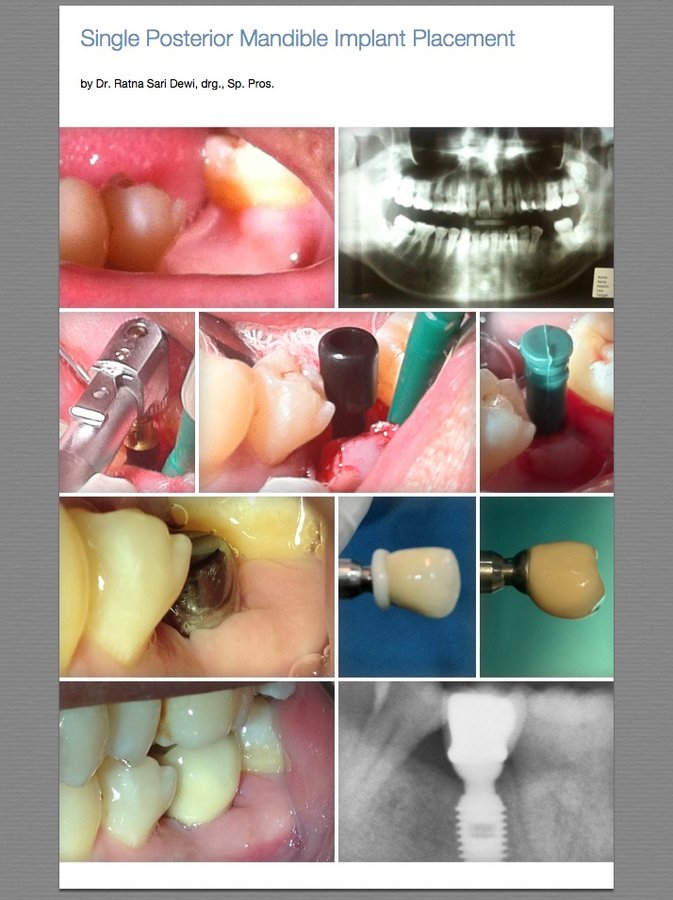

About RSD Dental Esthetic & Implant Center RSD Dental Clinic was built with the concept of one-stop-dental-care especially on Esthetic Dental Services and Dental Implants. We are also providing a full range of general dentistry treatments such as Oral Surgery, Braces, Dental Filling, Crown and Bridge, Gum Treatments, Teeth Whitening and many more in high quality services and reliable cost. Founded by Dr. Ratna Sari Dewi and her fellow... (Show more)